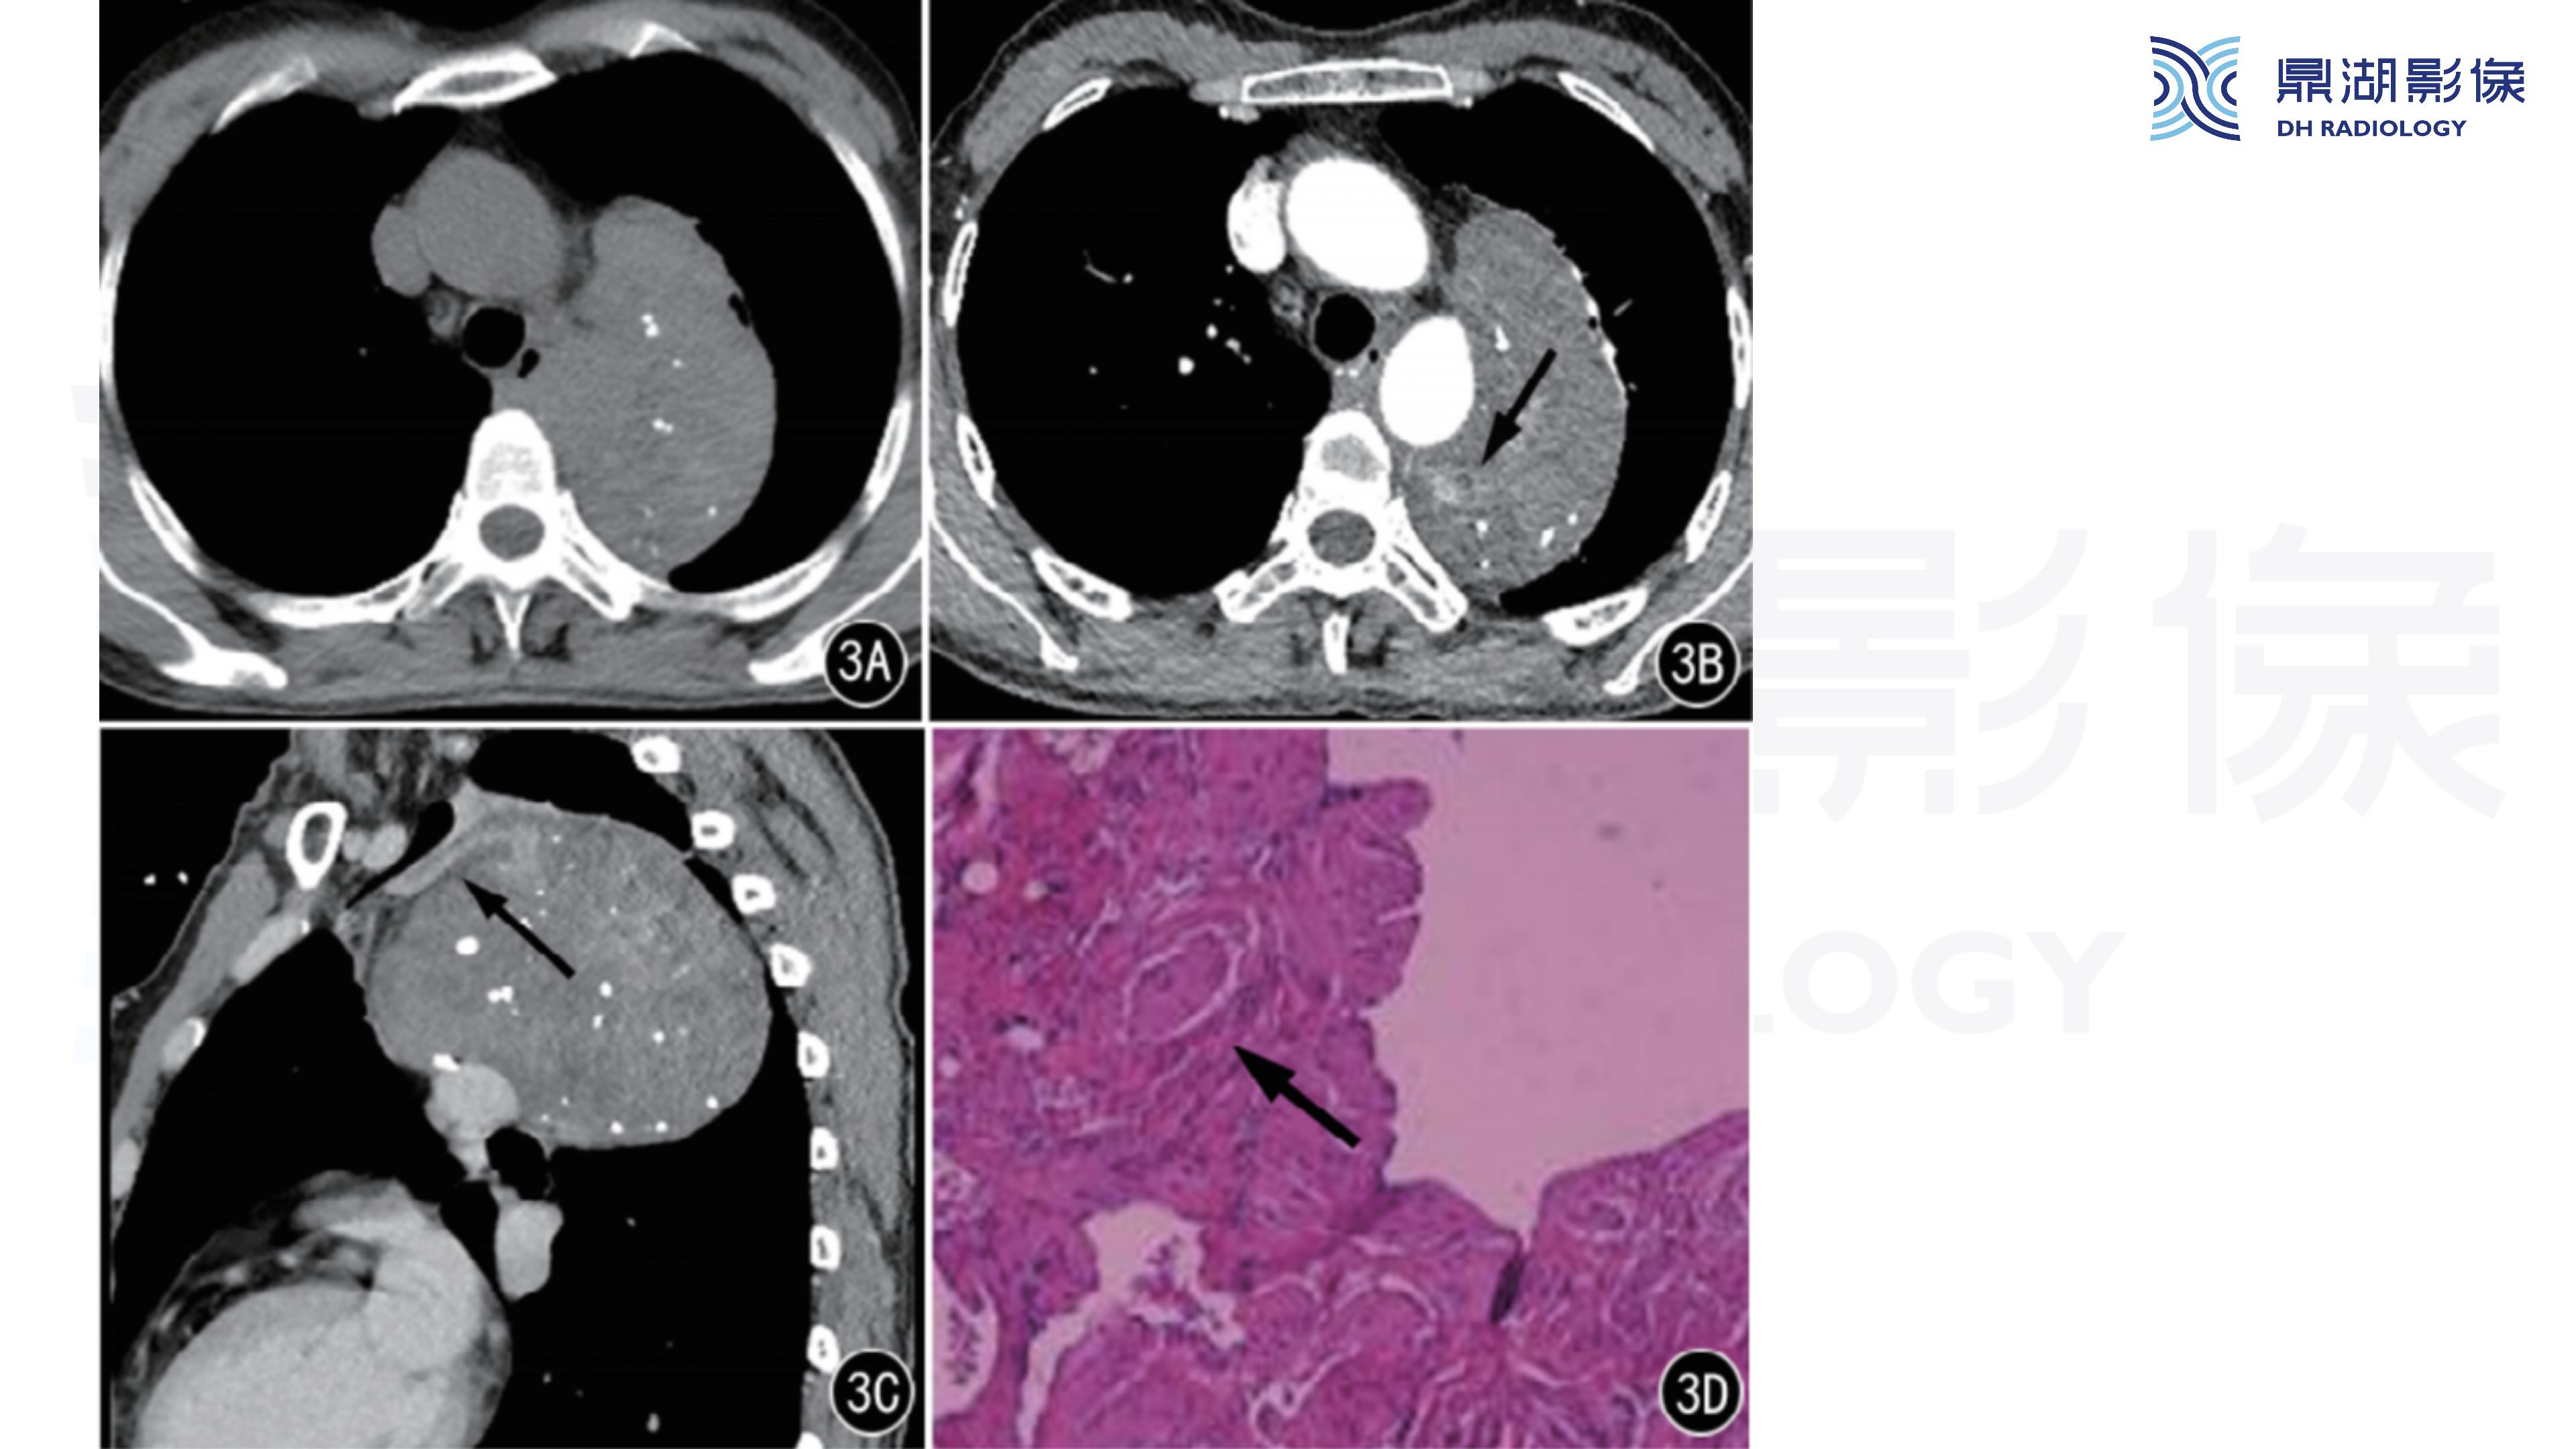

纵隔血管瘤-鼎湖社群读片病例